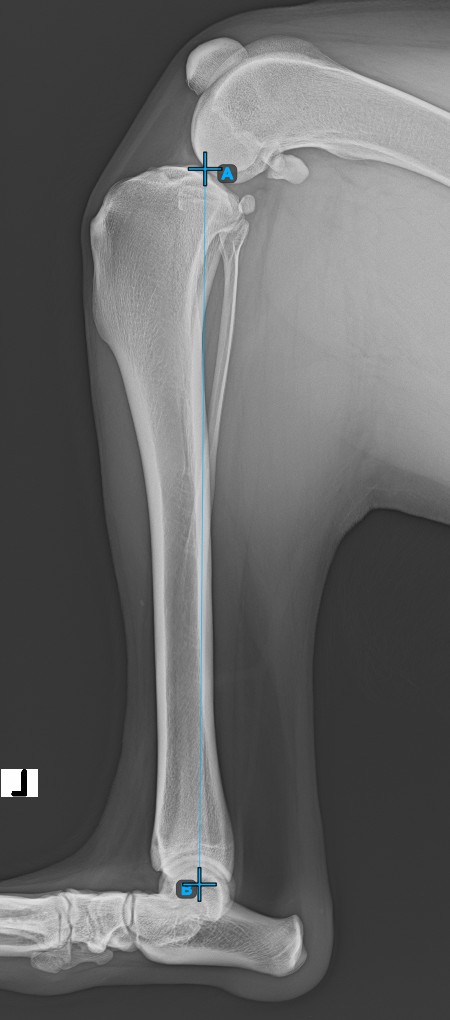

Starten Sie die Messung, indem Sie die Eminentia Intercondylaris markieren, die sich am Gelenk zwischen Femur und Tibia befindet.

Das Bild unten zeigt die übliche Platzierung des Punkts Eminentia Intercondylaris.

Fahren Sie fort, indem Sie den Mittelpunkts der Cochlea markieren, der sich am Ende des Tibiaknochens befindet. Die Linie zwischen der Eminentia Intercondylaris und dem Mittelpunkts der Cochlea stellt die Längsachse der Tibia dar.

Das Bild unten zeigt die übliche Platzierung des Mittelpunkts der Cochlea.